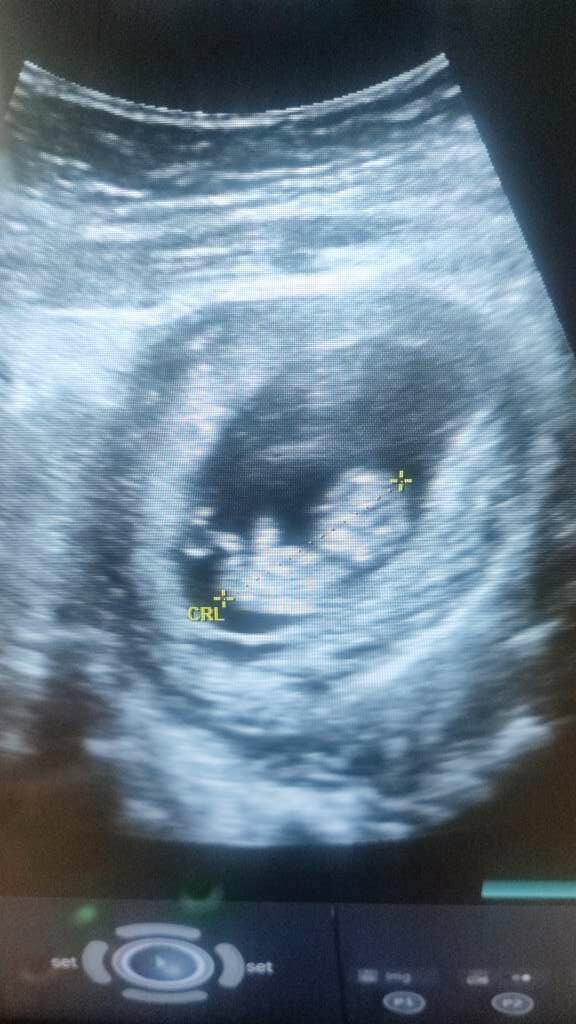

pod względem uciążliwych mdłości i mega zmęczenia, ten tydzień jest najgorszy